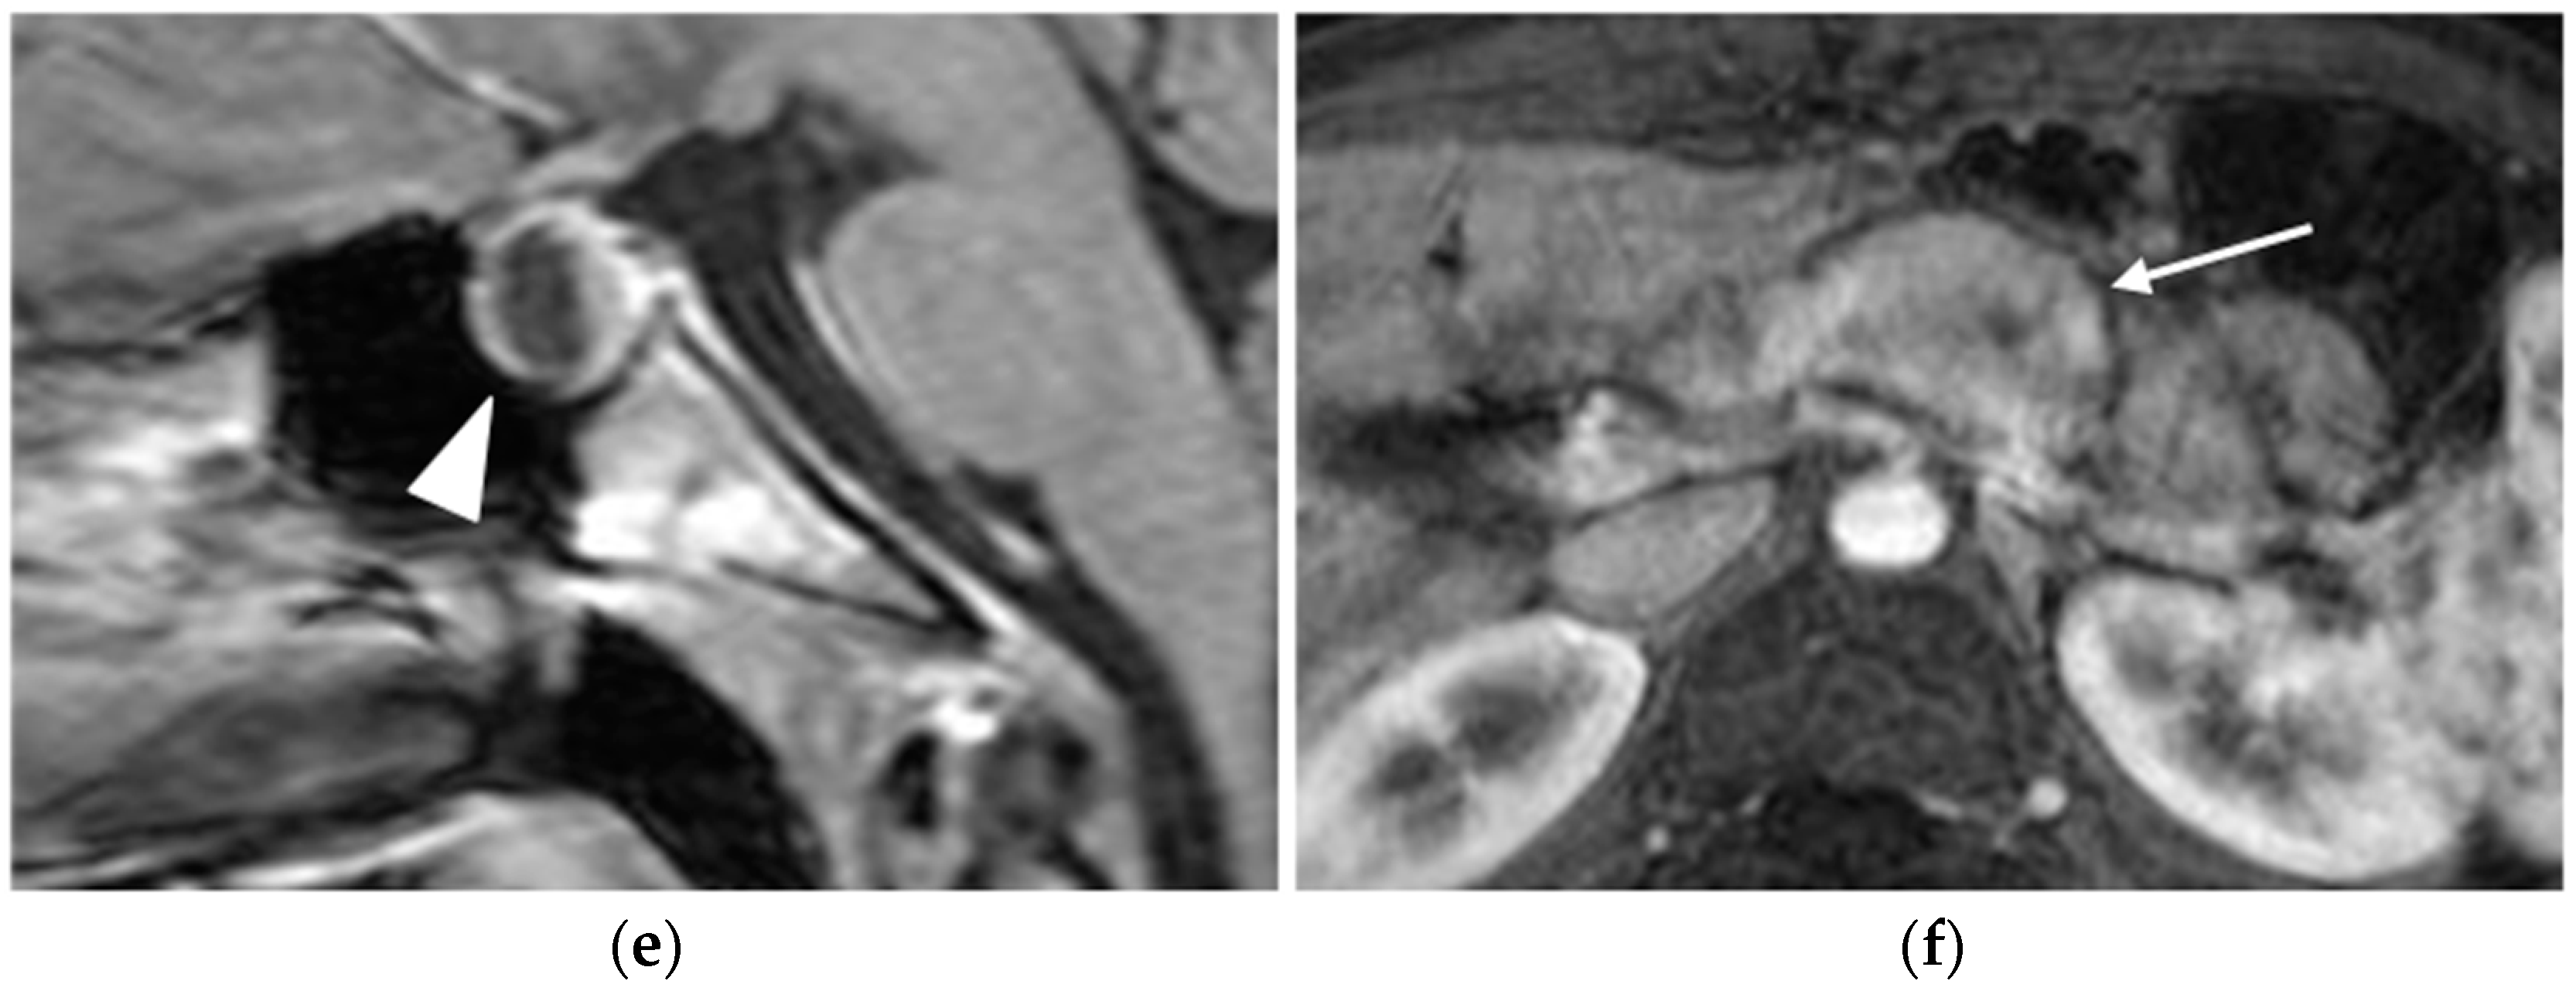

PNETs exhibit varying signal intensity with Diffusion-Weighted Imaging (DWI), but they often demonstrate restricted diffusion, with smaller lesions potentially being not easily detected on other MRI sequences [17]. Less differentiated tumors demonstrate even more diffusion restriction (Figure 6).

Figure 6.

Insulinoma. Heterogeneously enhancing mass (arrows) in the pancreatic tail (a), with significant diffusion restriction (b,c) and avid uptake on PET-CT (d).

After contrast administration, pNETs show hyperintensity in the arterial phase.